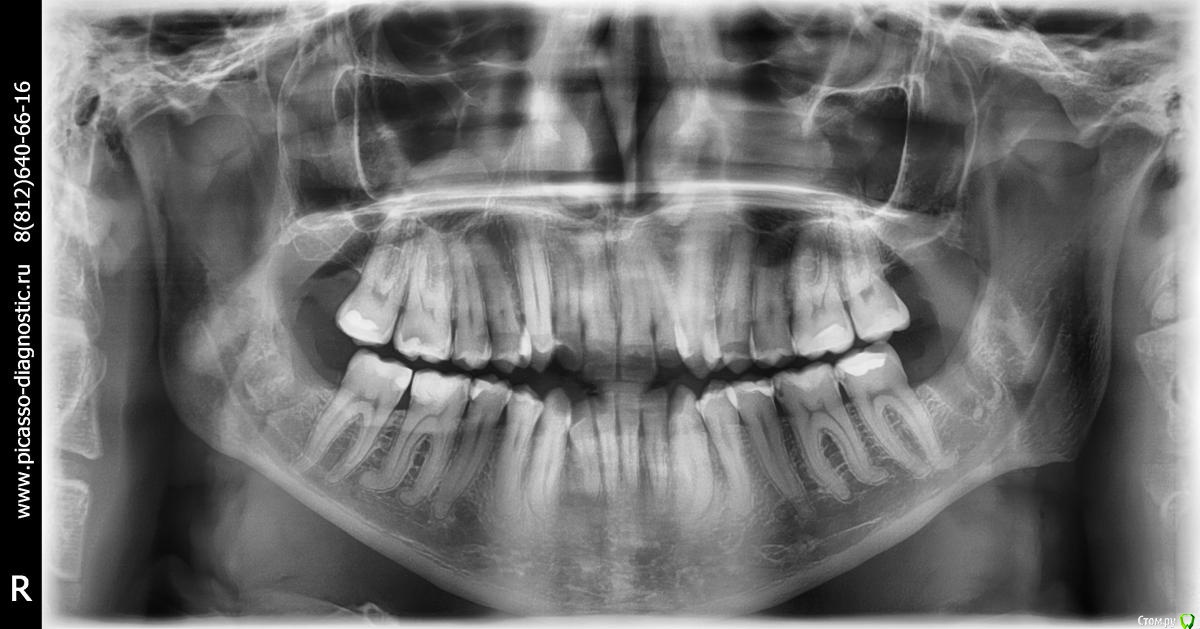

zab Опубликовано 6 октября, 2016 Поделиться Опубликовано 6 октября, 2016 Один врач говорит что так можно брекеты поставить, другой что надо вырывать 4.Спасибо тем кто даст дельный совет. Поделиться своей историей . Ссылка на комментарий

m.d.n Опубликовано 17 октября, 2016 Поделиться Опубликовано 17 октября, 2016 Можно , если вы хотите выровнять зубы и на последствия вам наплевать. Если же хотите и зубы выровнять и красиво выглядеть то и брекеты и операция . и зубы удалять ненадо. НО 1000000 рублей. Ссылка на комментарий

Brigita Опубликовано 26 октября, 2016 Поделиться Опубликовано 26 октября, 2016 (изменено) Я думаю, что скорее всего да- брекеты, подготовка, ортогнатическая операция.А фото покажите? Может и модели есть? Изменено 26 октября, 2016 пользователем Brigita Ссылка на комментарий